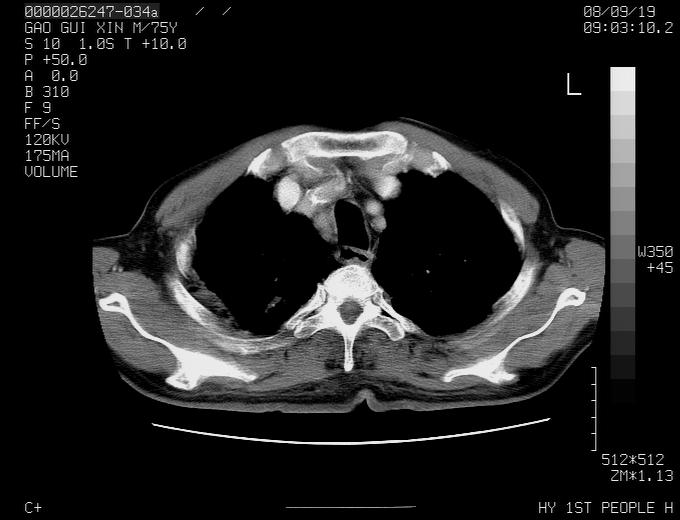

感谢各位老师的意见,左上肺病灶,我本人趋向结核,原因:左上肺见两个类圆形结节,仔细回顾4月份ct似乎原片在该处有条片状密度增高影,强化不明显。

现上传增强片,请各位老师仔细帮我看一下。

右上肺可见条索状影,并可见钙化,左上肺结节可以考虑为结核球,但气管前腔静脉后有肿大淋巴结,本人觉得左上肺结节不能排除转移瘤的可能,右上肺为陈旧性结核灶。

左肺上叶周围性肺癌并纵隔多组lnm.不可能是tb.

左肺上叶尖段瘢痕癌并纵隔淋巴结转移解释更好一些.

左肺周围癌并纵隔淋巴结转移,另一小结节是血管影

1)左肺上叶尖段周围型肺癌并纵隔淋巴结转移。2)冠状动脉及主动脉钙化。